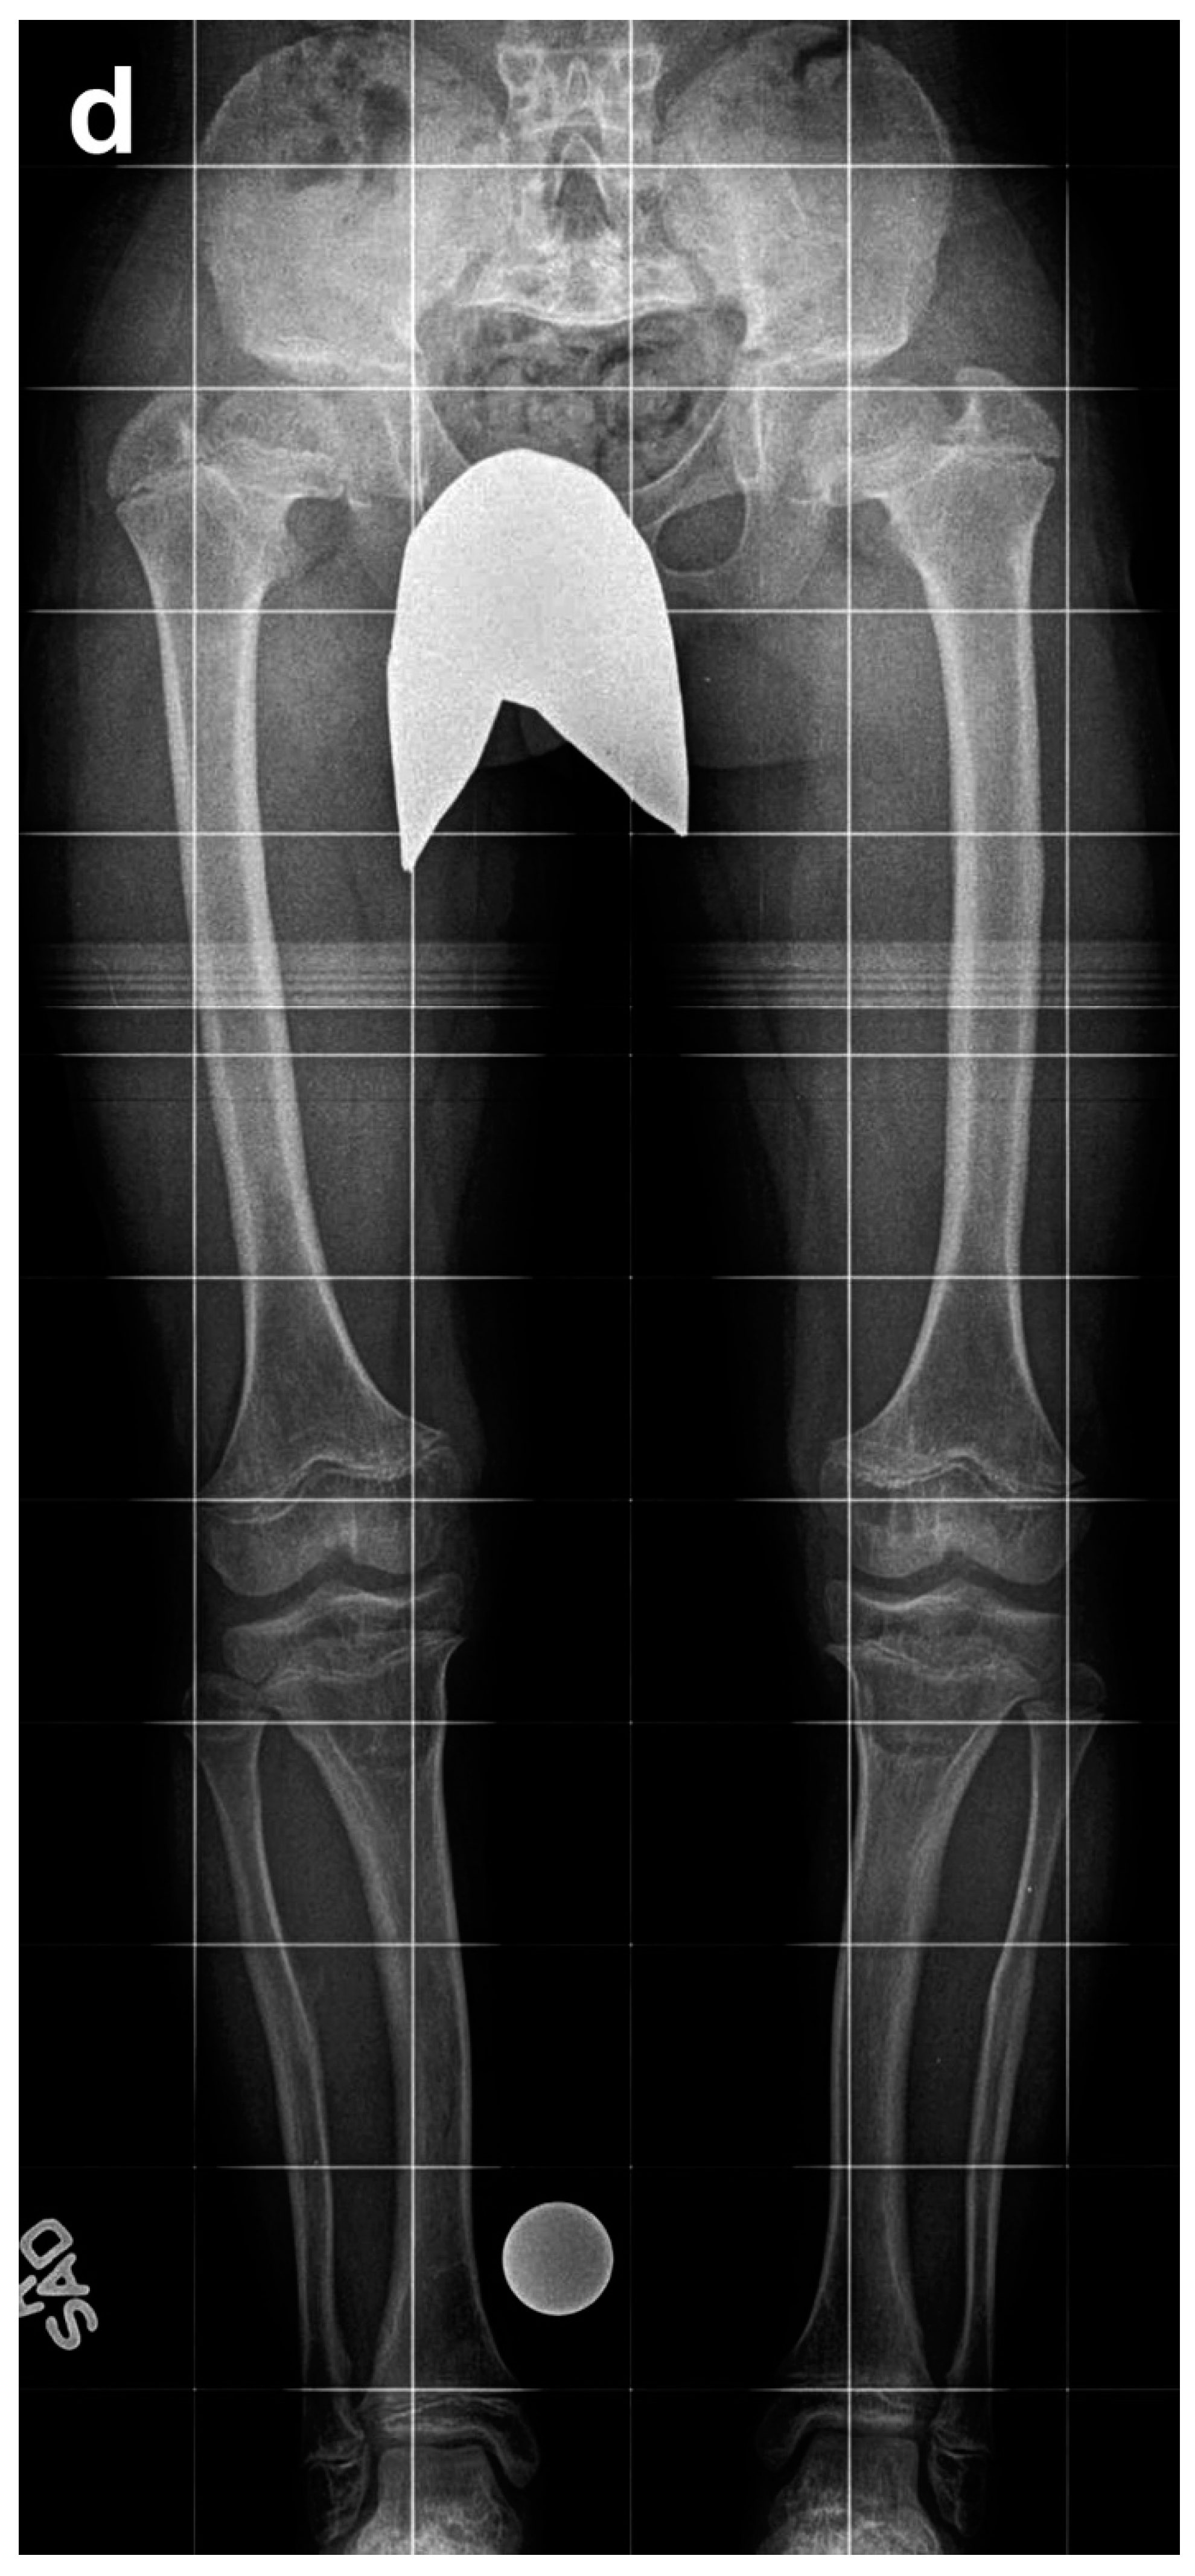

Figure 2. Eight-year-old boy who underwent two simultaneous bilateral femoral tibial lengthening (SBFTL) procedures. A Taylor Spatial Frame (Smith & Nephew, London, UK) was used for the tibia, and an Orthofix LRS (Lewisville, TX) was used for the femur. (a) Prior to first limb lengthening. (b) During first SBFTL. (c) Status after 10-cm lengthening. (d) Prior to second limb lengthening. (e) During second SBFTL. (f) Status after additional 12.5-cm lengthening (used with permission).

Of these 64 patients, nine patients were excluded as they underwent SBFTL using other methods of fixation, such as internal femoral nail or a combination of internal fixation for the femur and external fixation for the tibia. An additional five patients did not have at least 12 months of follow-up after external fixation removal and were excluded from this analysis. Fifty patients (29 males, 21 females, 200 bone segments) with achondroplasia met our inclusion criteria and underwent a total of 65 lengthening procedures (260 bone segments underwent lengthening). We defined a “procedure” as SBFTL (Figure 2).